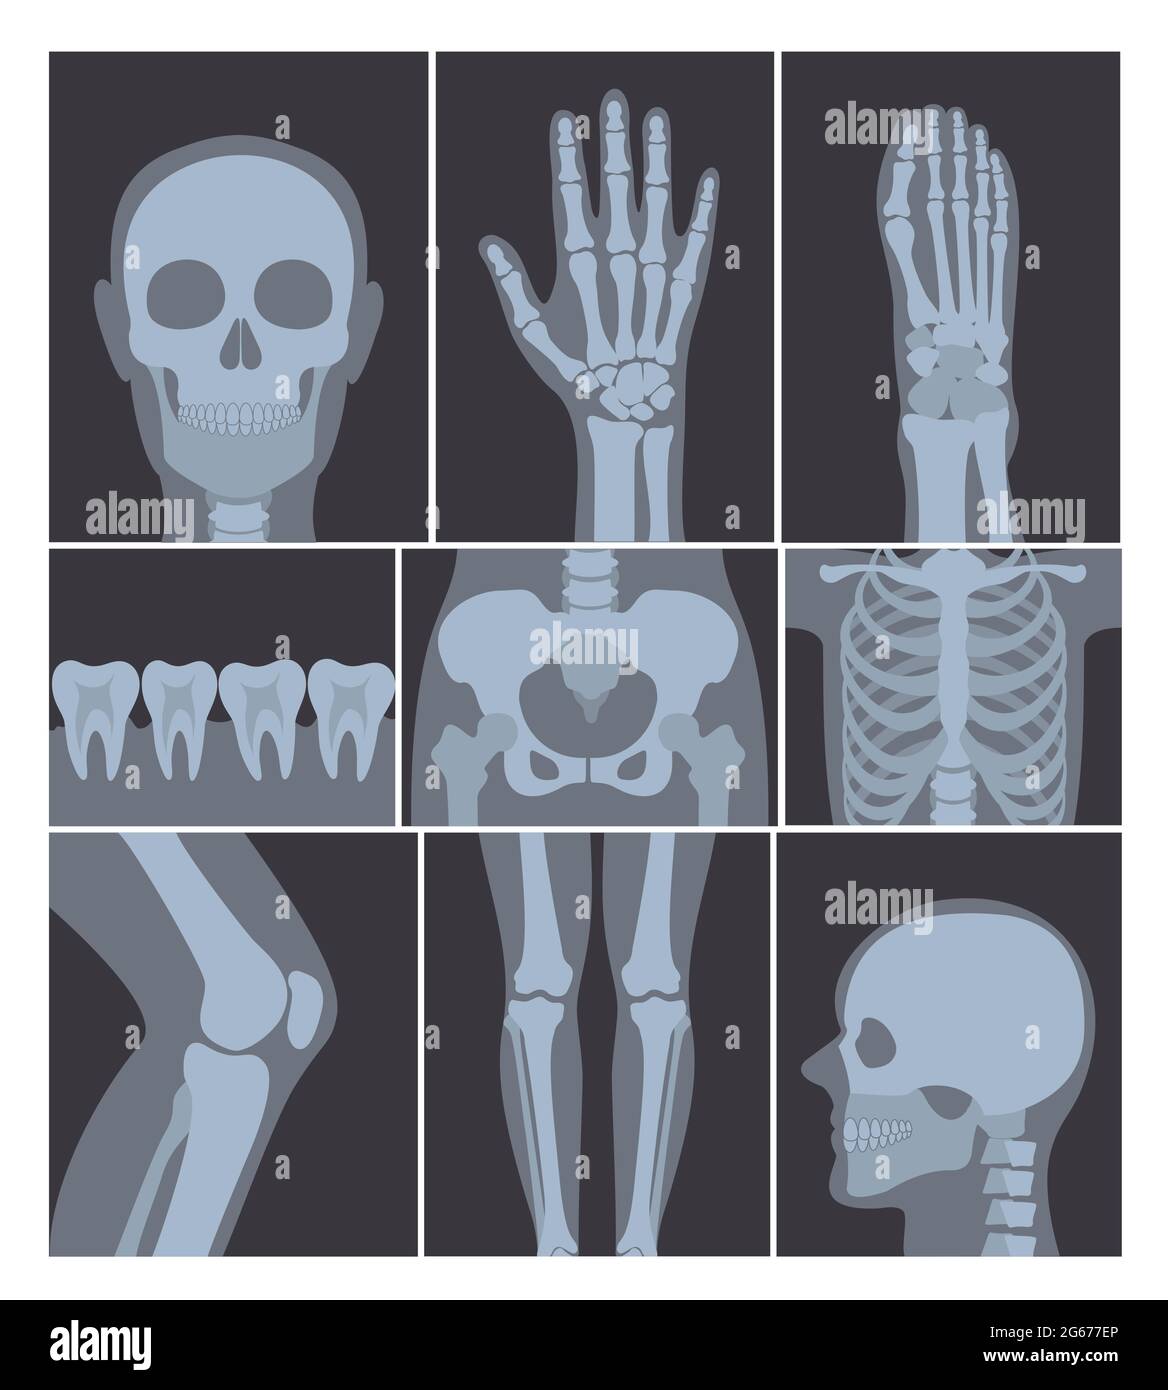

RF2BE8ME8–Collection d'os humains sur tableau de surveillance. Squelette de l'anatomie humaine, de la colonne vertébrale et de l'os de la main. Illustration vectorielle

RF2G677EP–Ensemble d'illustrations vectorielles de tirs de rayons X. Main, tête, genou et autres parties du corps humain sur des clichés radiographiques sur fond blanc.

RF2G6790K–Ensemble d'illustrations vectorielles de nombreux clichés de rayons X du corps humain, images radiographiques de la tête, des mains, des jambes et d'autres parties du corps sur fond blanc.